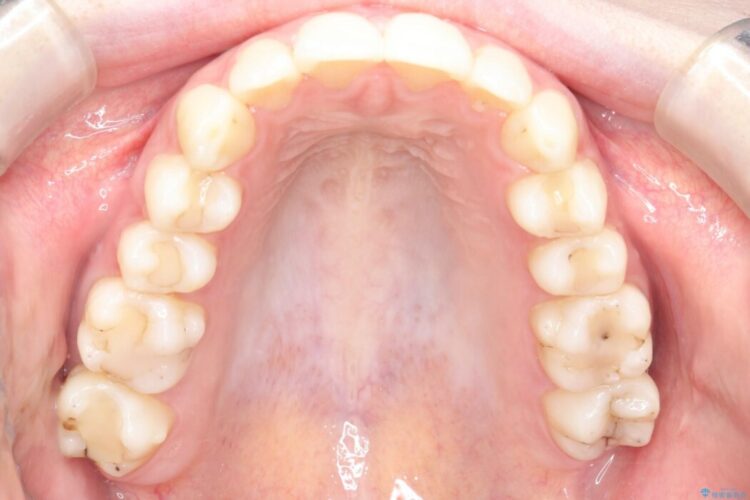

上下顎の歯列のガタつきを治したいとのことで来院されました。

全体的に少し内側へ傾斜しているのが確認できました。そのため歯列弓が狭まり噛み合わせにも影響しています。

まずは奥歯を後ろへ遠心移動をさせながらがたつきを改善していくマウスピース矯正をご提案しました。